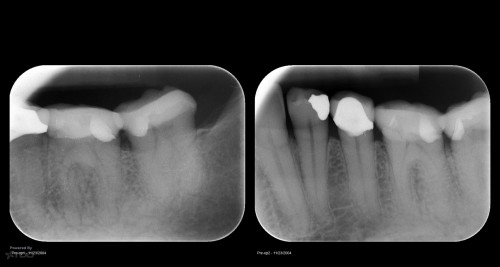

Disappointing recall

By Gary Carr / July 5, 2018

Busy recalling cases from the 10-15 yr time frame. Had I just done 5 yr […]